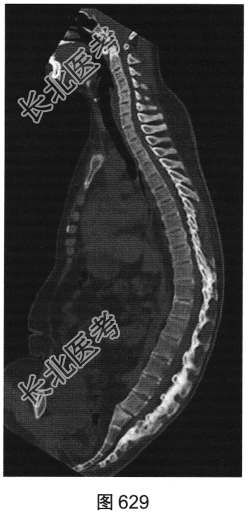

- 多项选择题2.[提示]患者行脊椎及骶髂关节CT检查,见图629~图631。该患者CT图片有哪些阳性征象( )

D、椎旁韧带骨化

E、胸腰段后凸畸形

F、双侧骶髂关节及脊椎椎小关节间隙消失

G、竹节椎